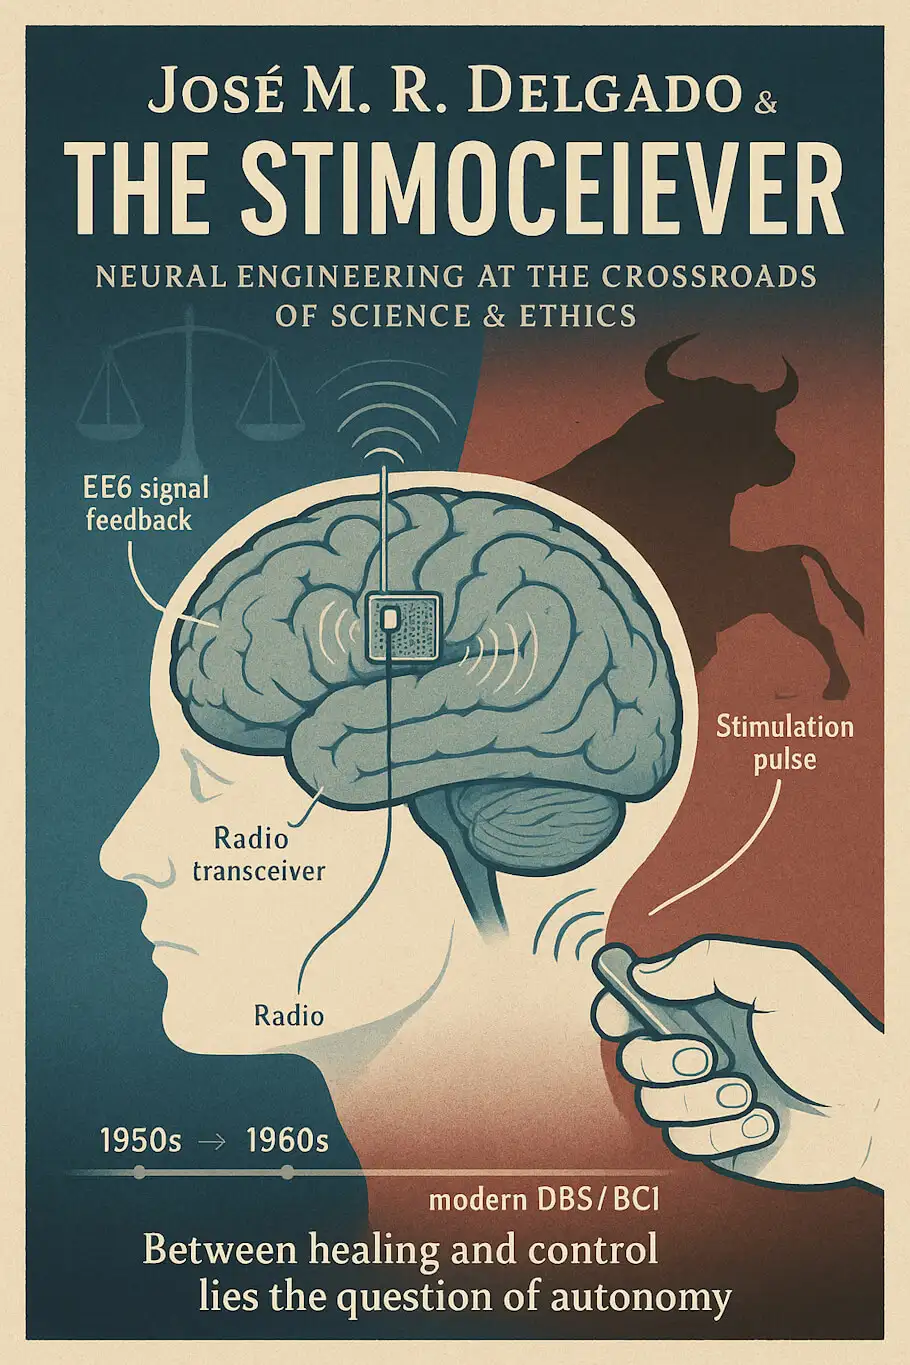

早期的大脑刺激实验需要将电线从动物的大脑连接到笨重的外部设备上,这不仅限制了动物的活动范围,还增加了感染风险。德尔加多决定改变这一切。他发明了"刺激接收器”——一个微型化的无线设备,可以完全植入头皮下,通过电磁线圈穿过皮肤供电。

这个设备具有双向通信能力:它不仅能向大脑特定区域发送电脉冲,还能记录脑电图数据并通过无线电传回给研究者。德尔加多称其为"与大脑的两路通信”。一些版本的刺激接收器甚至小到只有半美元硬币大小——在1960年代,这是令人惊叹的技术成就。

德尔加多开创的技术为现代深部脑刺激(DBS)奠定了基础,这是帕金森病、特发性震颤、强迫症和难治性抑郁症的标准治疗方法。DBS涉及在特定大脑结构中植入电极,持续输送电刺激以调节神经活动。成千上万的患者从这些干预中受益,运动功能和生活质量获得了戏剧性改善。如果没有德尔加多和他的同代人所做的那些基础研究,这一切都不可能实现。

刺激接收器的概念本身预示了当代的脑机接口和响应性神经刺激系统。现代脑机接口允许瘫痪患者通过神经信号控制电脑光标、机械臂和通讯设备。用于癫痫的响应性神经刺激系统自动检测癫痫活动并提供反向刺激,就像德尔加多1960年代的系统一样。这些技术正逐渐从实验走向临床应用,为患有毁灭性神经系统疾病的患者带来希望。

脑机接口正在快速推进,由军事和商业投资共同驱动。埃隆·马斯克的Neuralink公司设想了一个未来,大脑植入物允许直接的神经控制计算机,甚至脑对脑交流。虽然当前的应用集中在医疗用途——例如恢复瘫痪患者的行动能力——但长期愿景明确包括认知增强和扩展人类能力。